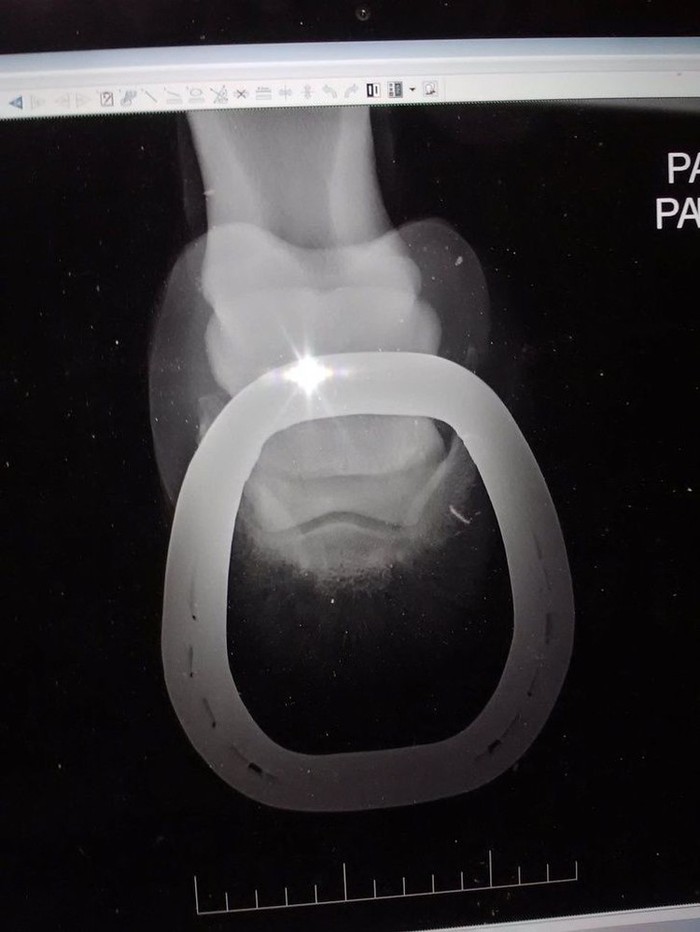

Penasaran bagimana hasil sinar X kaki kuda? begini hasilnya. (Foto: Brightside)